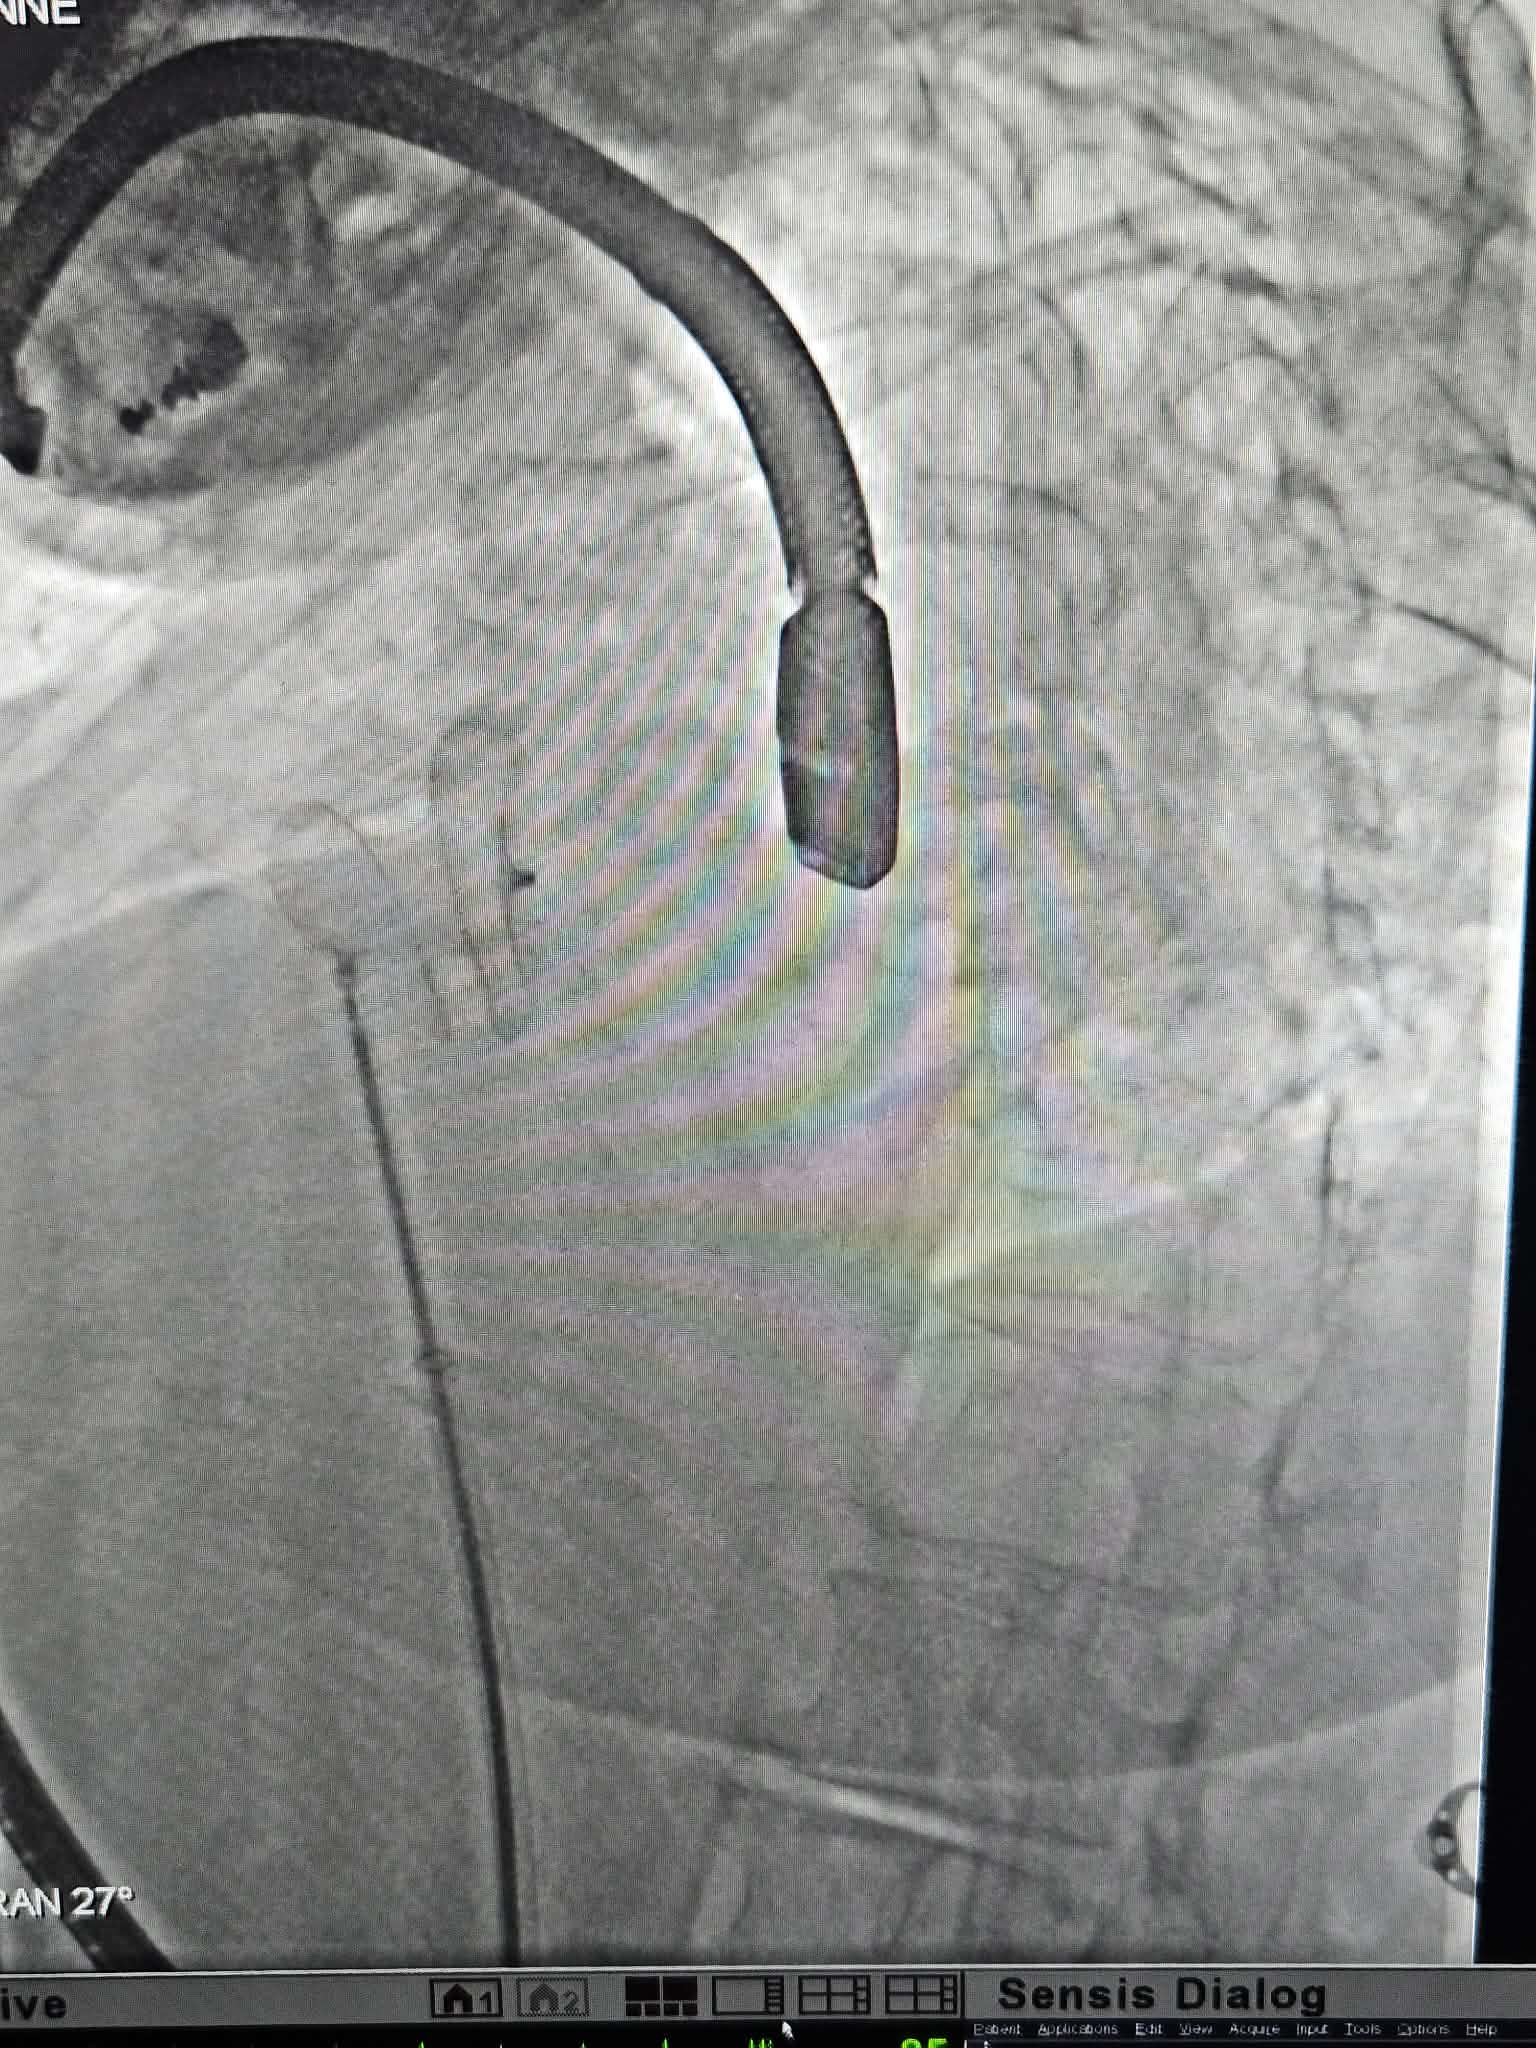

Μια πρωτοποριακή για την Κεντρική Ελλάδα ιατρική πράξη πραγματοποιήθηκε με απόλυτη επιτυχία στο ΙΑΣΩ Θεσσαλίας, επιβεβαιώνοντας τον διαρκώς αναβαθμισμένο ρόλο του Νοσοκομείου στην αιχμή της σύγχρονης επεμβατικής καρδιολογίας. Πρόκειται για διαδερμική σύγκλειση μεσοκολπικής επικοινωνίας, μιας από τις πιο κοινές συγγενείς καρδιοπάθειες, μια εξειδικευμένη και υψηλής τεχνικής δυσκολίας επέμβαση, η οποία πραγματοποιήθηκε για πρώτη φορά με επιτυχία στην περιοχή, αποκλειστικά στο ΙΑΣΩ Θεσσαλίας, στο υπερσύγχρονο Αιμοδυναμικό Εργαστήριό του.

Υπεύθυνος ιατρός της επέμβασης ήταν ο Νίκος Μαγκούτης, MD, MSc, PhD, Επεμβατικός Καρδιολόγος, Διευθυντής και Επιστημονικά Υπεύθυνος του Αιμοδυναμικού Εργαστηρίου, με τη συνεργασία εξειδικευμένης ομάδας ιατρών. Ειδικότερα, στην επέμβαση συνέβαλλαν ο Όμηρος Χαλβατζούλης Χειρουργός Θώρακος Καρδιάς Μεγάλων Αγγείων, Επιστημονικά Υπεύθυνος Καρδιοθωρακοχειρουργικού Τμήματος, η Αναισθησιολόγος Σμαραγδή Σαρχώση, ο Καρδιολόγος Αργύρης Γκαρμπούνης, η Αναισθησιολόγος Ευαγγελία Νέου και η ομάδα των εξειδικευμένων τεχνολόγων και νοσηλευτών του Αιμοδυναμικού Εργαστηρίου του ΙΑΣΩ Θεσσαλίας. Στην επέμβαση συμμετείχε και ο Βασίλειος Θανόπουλος, Αναπληρωτής Καθηγητής και Επεμβατικός Καρδιολόγος Συγγενών Καρδιοπαθειών, με πολυετή εμπειρία σε σύνθετες διακαθετηριακές επεμβάσεις.

Η άριστη έκβαση της πρωτοποριακής αυτής επέμβασης αναδεικνύει το υψηλό επίπεδο επιστημονικής επάρκειας, ασφάλειας και συνεργασίας της ιατρικής ομάδας του ΙΑΣΩ Θεσσαλίας. Με κορυφαίους ιατρούς, υπερσύγχρονο εξοπλισμό και εξειδικευμένες μονάδες, το ΙΑΣΩ Θεσσαλίας αποτελεί μοναδικό κέντρο αναφοράς για την ευρύτερη περιοχή, προσφέροντας στους πολίτες της Κεντρικής Ελλάδας ό,τι πιο σύγχρονο διαθέτει η ιατρική επιστήμη στην πρόληψη και θεραπεία των καρδιαγγειακών παθήσεων.